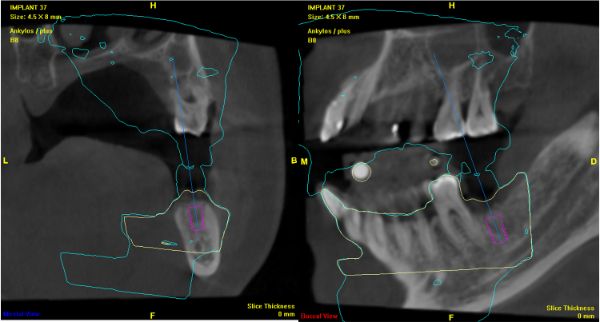

電腦定位手術模板

下顎最佳植牙位評估